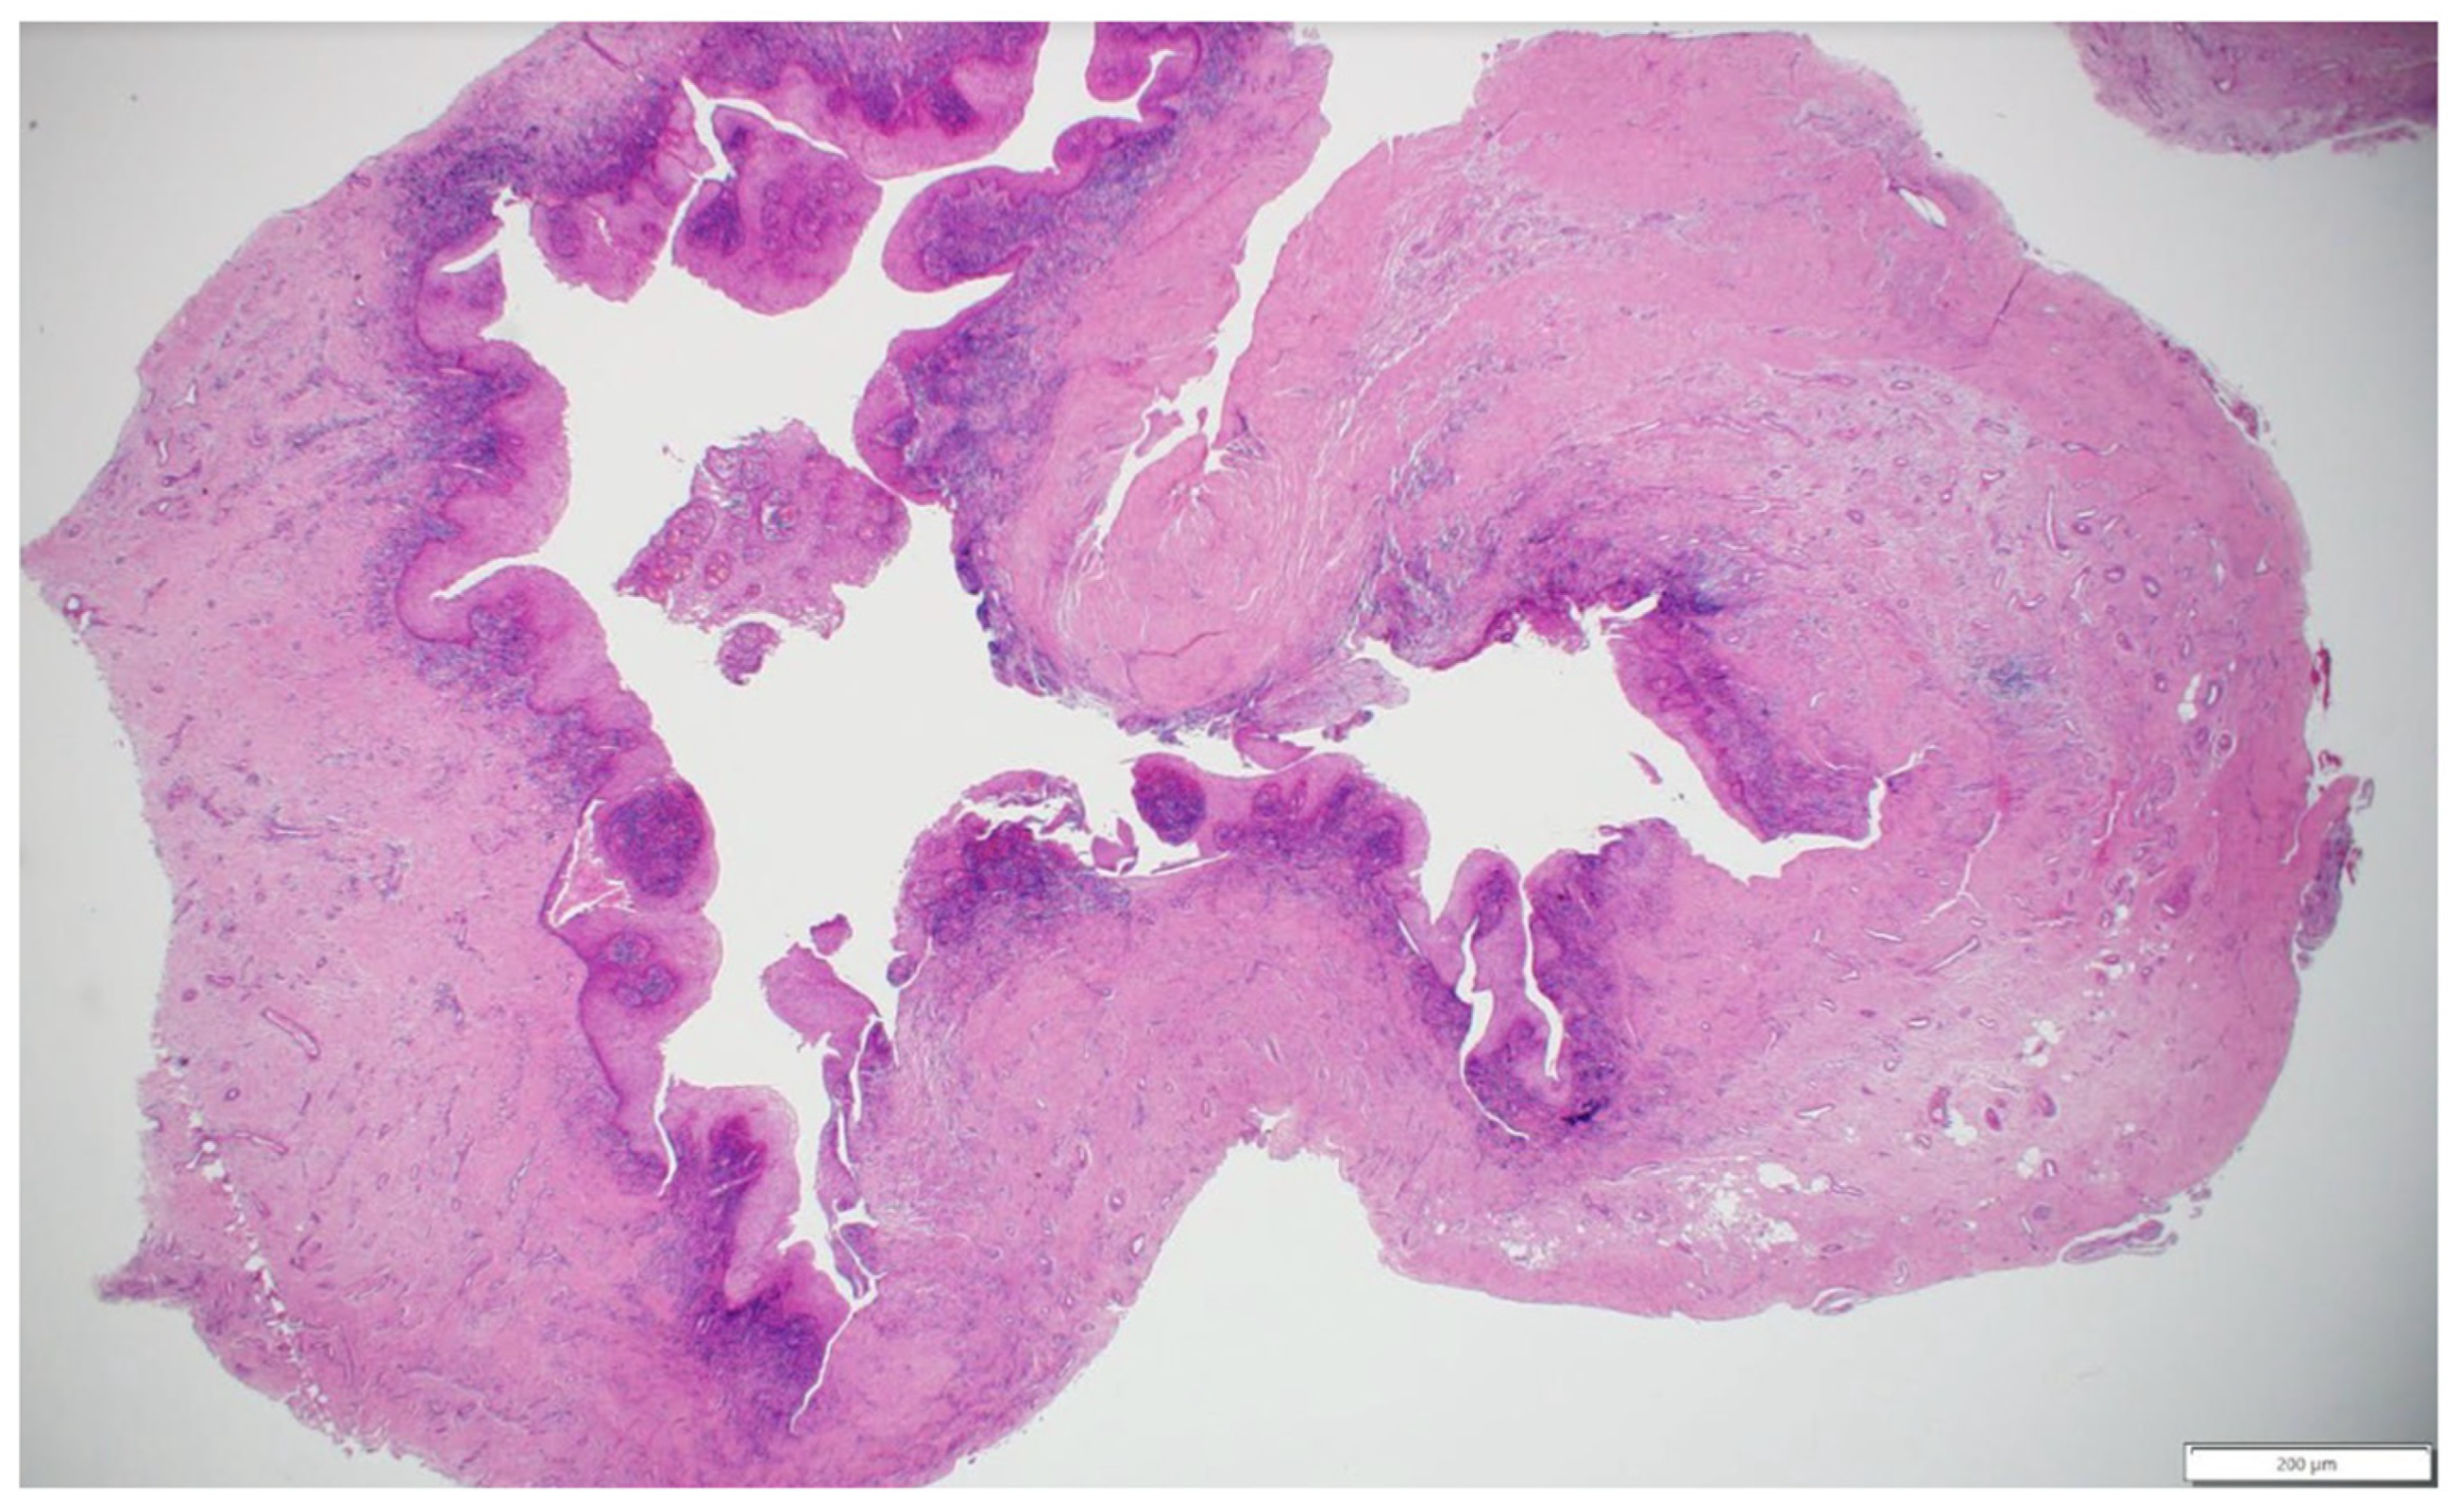

2.4. Histopathological Findings

Histopathological analysis (Figure 5) of the excised cystic lesion revealed a cystic structure lined by hyperplastic, non-keratinized odontogenic epithelium exhibiting squamous metaplasia. Several luminal epithelial cells displayed a characteristic “hobnail” appearance, demonstrating epithelial remodeling. The connective tissue wall was thick and highly collagenous, with chronic inflammatory infiltrates predominantly localized adjacent to the epithelial lining. Additionally, the connective tissue contained multiple large blood vessels and several nerve fibers. These findings, along with the clinical and radiographic correlation, confirm that the lesion represents a periapical inflammatory cyst arising from a non-vital tooth.

Figure 5.

Histopathological features of the excised periapical inflammatory cyst, showing non-keratinized odontogenic epithelium with squamous metaplasia and “hobnail” cells, a thick collagenous wall with chronic inflammatory infiltrate, and prominent vasculature and nerve fibers in the connective tissue (hematoxylin and eosin stain, scale bar = 200 μm).